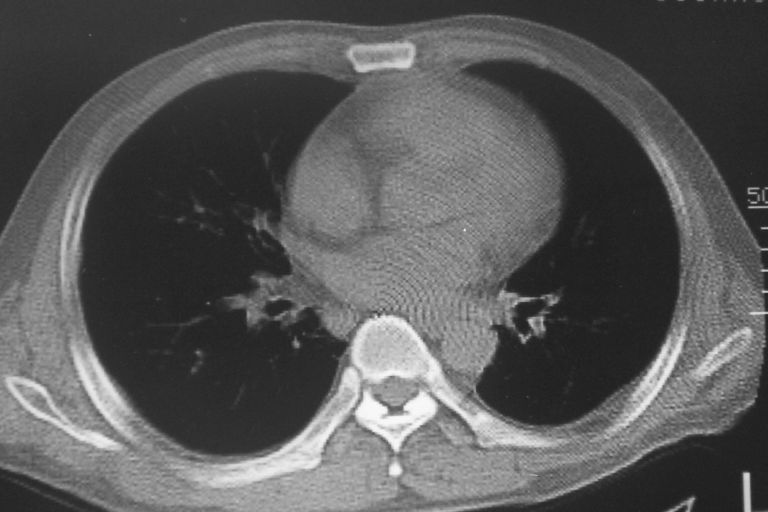

标题: CT10574:男 50岁胸部CT请会诊!

患者 男 50岁 无痛性咯血3天,无其他不适.

左下肺结节状软组织密度影,边缘有毛刺,考虑周围型肺癌。

1 左肺下叶基底段见两结节软组织密度灶, 肺窗边缘见有毛刺征像, 不能排除占位. 2 建议结合临床治疗一周后ct随访在看其结果.

临近胸膜增厚,病变周围肺不清,稍有分叶。结节密度略高,肺、纵隔窗差异不大,肺癌待排。前方还有一个

左下肺结节状软组织密度影,一个边缘有卫星病灶,邻近胸膜增厚.另一个有毛刺.心影周围水样密度影环绕.考虑:

1.肺癌可能.肺tb待排.

2.左侧胸膜增厚.心包积液.